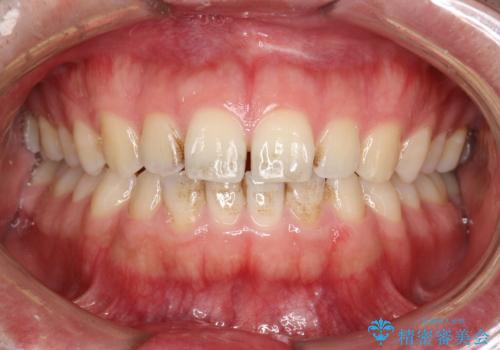

PMTCで前歯の着色・ステインを綺麗に

- 前歯の着色・ステインが歯磨きで取れないため綺麗にしてほしいとのことで来院されました。PMTC30分コースを行いました。